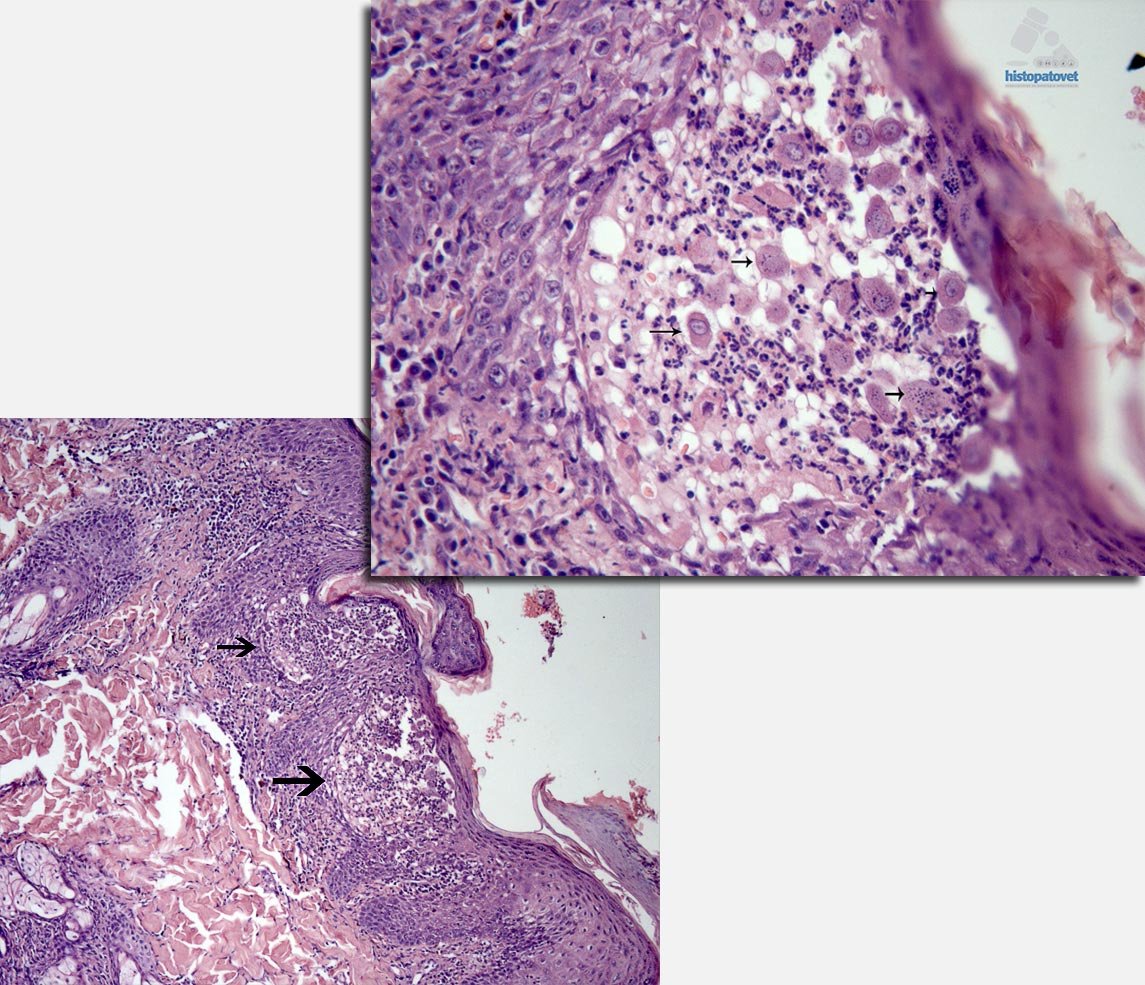

Se reciben dos pequeños punchs dérmicos. La epidermis, presento una hiperqueratosis ortoqueratótica con formación de costras( Fig4.).

En varias partes los queratocitos muestran palidez, con zonas de degeneración, provocando necrosis y separación de ellos. Como consecuencia se formaron cavidades( pústulas), con presencia de polimorfonucleares y queratocitos libres(Fig5. y 6.).

Los hallazgos histopatológicos son de una enfermedad autoinmune del grupo de los pénfigos. Los cambios morfológicos son similares a los descritos en el PÉNFIGO FOLIÁCEOS, con una presentación predominantemente NASAL.

Pénfigos foliáceos es una enfermedad PUSTULAR. Sin embargo, la lesión puede empezar como una pápula, para luego de forma rápida convertirse en pústula. Posteriormente provoca erosiones y costras. Por esto, la principal muestra diagnóstica especialmente para histopatología, en una pústula intacta. Tengan en consideración que este paciente ingreso por una lesión costrosa en el plano nasal, es decir la fase clínica pustular ya había pasado, sin embargo fue posible verla histológicamente.

Cuando sucede un impedimento en la adhesión o unión de los queratocitos, esto provoca la separación de las células, causando un fenómeno conocido como ACANTOLISIS.

En general en el caso de pénfigos foliáceos, los auto anticuerpos actúan contra los antígenos presentes en la desmogleina-1 y otras moléculas de adhesión celular.